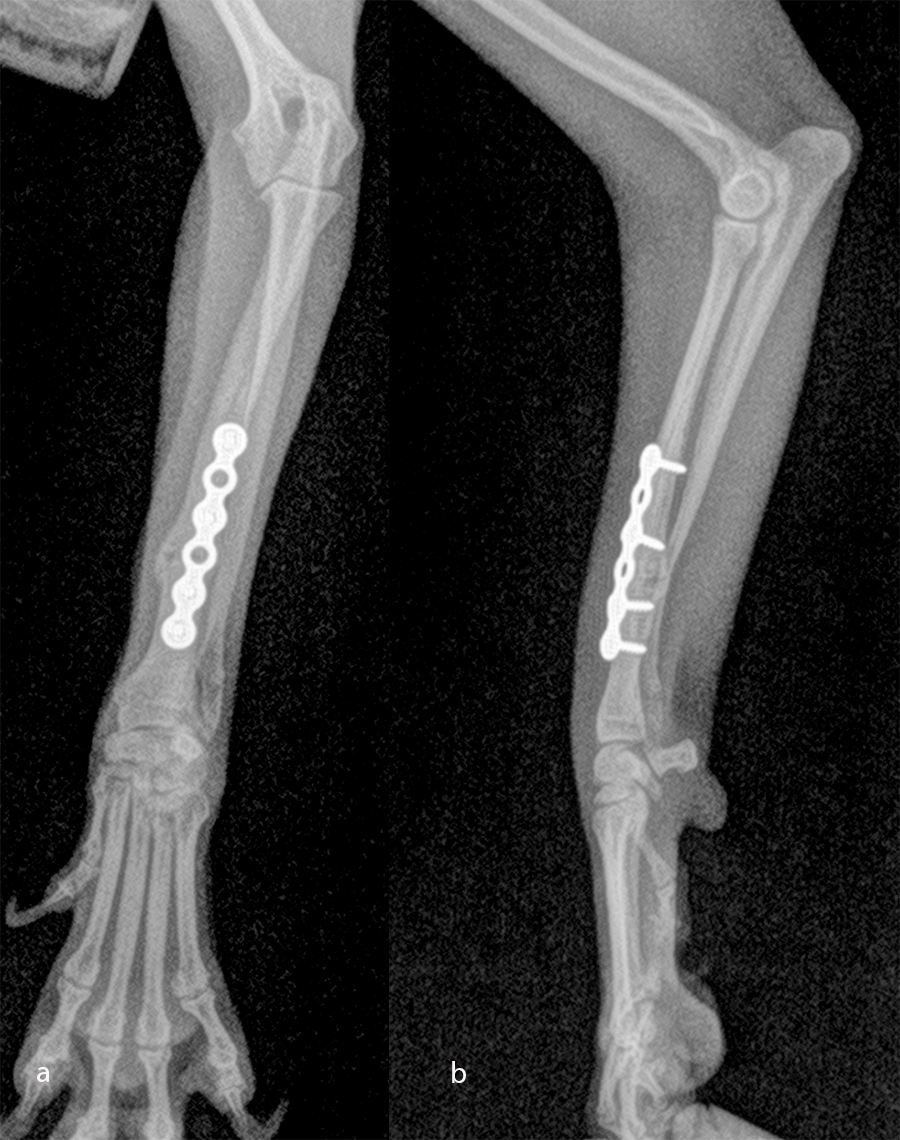

Open reduction and internal fixation of distal radial and ulna fractures with a single 1.3 radial plate (Fig 6).

The patient was a 6-month-old, 1 kg (exactly 0.950 kg) Pomeranian dog presenting with a radial fracture of the left thoracic limb after a jump from ≈ 50 cm. The 1.5 mm System was too large for the width of the radius (2.2 mm) and the width of the radial medullary canal (0.5 mm) (Fig 7). The 1.3 mm adaptation plate was a perfect plate for this fracture. This plate option permitted the use of cortex and locking screws.

An open but do-not-touch approach was performed, and the plate was fixed with one proximal and one distal cortex screws and one proximal and one distal locking screws (Fig 8). After 1 month the fracture of the radius was healed, and the dog had a complete functional recovery (Fig 9).